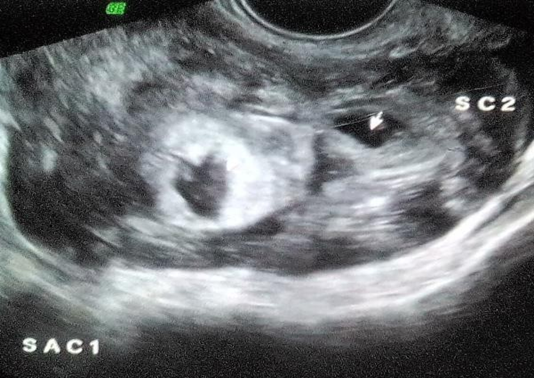

Transvaginal Sonography showed a heterogeneous mass in right adnexa measuring approximately 7.3 x 4.6 cm The mass showed irregular Gestational sac measuring approximately 0.3 cm corresponding to 5 weeks and another irregular sac measuring 0.5 cm corresponding to 5weeks 2 days Right ovary was visualised separately from this mass .

Left ovary was visualised and appears normal .Moderate hemoperitoneum was seen .Uterus was bulky however there was no intrauterine gestational.

Figure 3: Trans vaginal Sonography shows Right adnexa heterogenous mass with two irregular sacs and hemoperitoneum. Left ovary is visualised